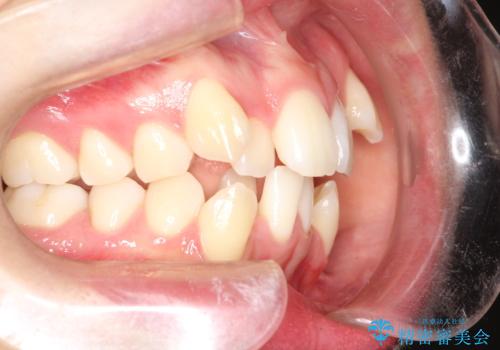

- 八重歯と前歯のガタガタを主訴に来院されました。

目立たない装置をご希望でしたので、上下左右の歯を1本ずつ抜歯してハーフリンガルでの矯正を行いました。